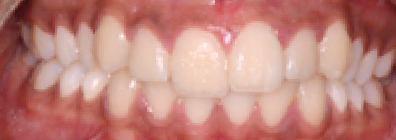

Le résultat de fin de traitement est satisfaisant. Le profil de la patiente est harmonisé. Une contention fixe mandibulaire et maxillaire de canine à canine est choisie.

À propos du cas, on note la persistance d’une petite classe II squelettique (ANB = 5°). Cependant, l’axe de l’incisive maxillaire ne permet pas une correction plus importante de la classe II par avancée mandibulaire car le surplomb est déjà faible et l’incisive maxillaire est légèrement versée (106°). Les axes de 11 et 12 auraient pu être améliorés.